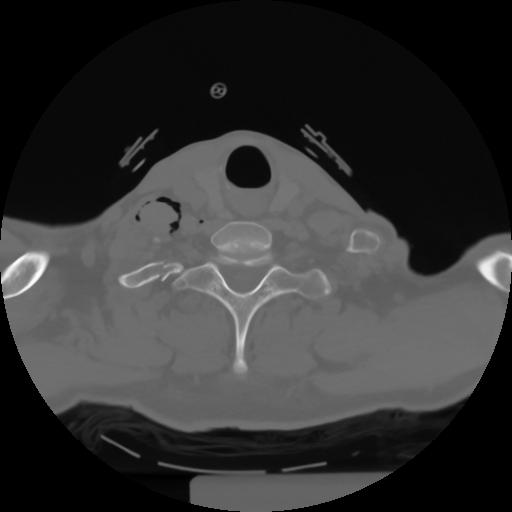

10 P.BLANDAS,,Axial,2.0,P.BLANDAS,,